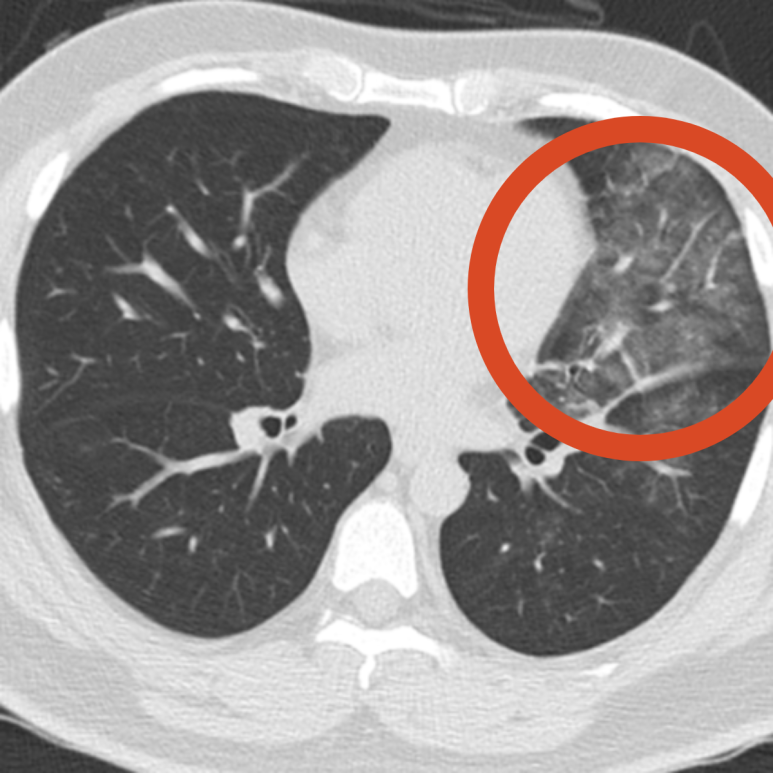

발열, 기침으로 오셔서 폐렴이 발견된 사례